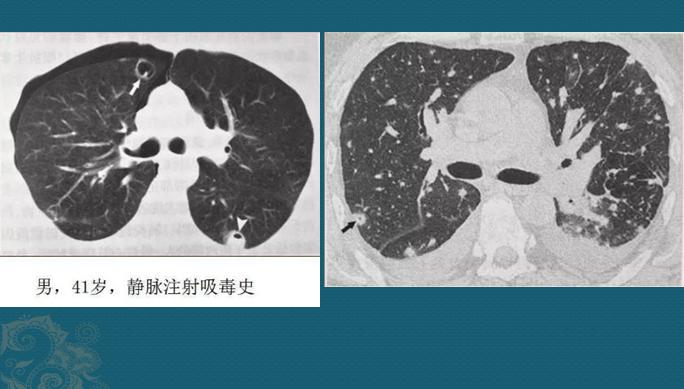

如果它们抵达肺部小血管周围生根发芽,就会制造各种毒素引发炎症,表现为多发点片状影或类圆形结节影,边缘清晰或模糊,沿支气管血管束或肺外周和基底部分布,因为是化脓性感染,多数结节最后会坏死、液化,形成空洞,当损伤血管或者形成血管内菌栓堵塞还可以引起远侧肺组织缺血坏死(肺梗死),形成胸膜下楔形肺实变影。

血源性金葡菌肺炎

这些都是金葡菌小草刚发芽,多发小结节、小斑片影,有的形成了小空洞和小气囊,部分与血管关系密切,提示病菌是从血道来源引起肺部播散,及时抗生素治疗可以压制炎症发展。

而如果治疗不及时、细菌毒力强、菌量过多、或者抗生素使用不合理、病人有基础疾病体质差等原因,双肺炎症会快速进展,就会出现大片肺实变,多发磨玻璃影,多发小空洞小气囊,靠近外围的气囊破裂还可引起脓气胸和皮下气肿,甚至出现白肺……